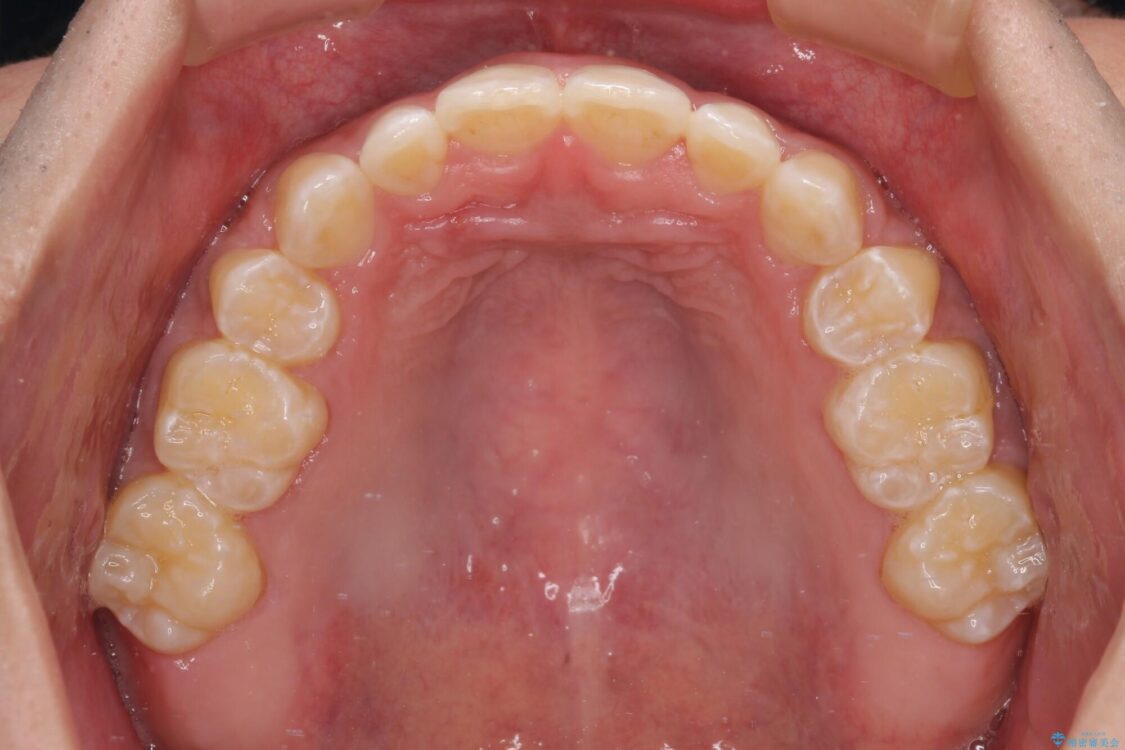

治療前

• 口元の突出感を改善 受け口傾向の咬み合わせの抜歯矯正 治療前画像